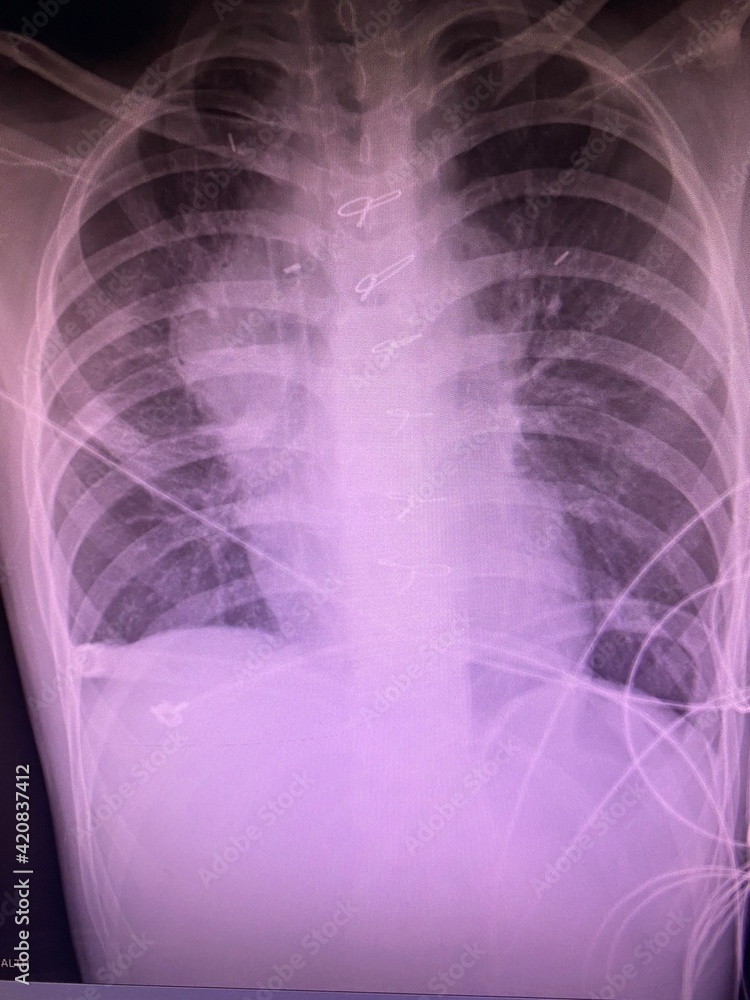

Film Chest Xray Show Alveolar Infiltrate At Left Middle Lung Stok Will A Chest X-Ray Show Mold Exposure Inhaling certain types of mold can cause. Mold exposure symptoms can be combated if you know what to look for. Yet the effects of mold. Mold grows in dark, damp places, like. Doctors may conduct a physical examination and take a medical history to determine if mold exposure is a possible cause of symptoms. Mold exposure can be difficult to. Will A Chest X-Ray Show Mold Exposure.

Film Chest Xray Show Alveolar Infiltrate At Left Middle Lung Stock Will A Chest X-Ray Show Mold Exposure — mold is a type of fungus. Yet the effects of mold. — frequent symptoms of mold exposure. Doctors may conduct a physical examination and take a medical history to determine if mold exposure is a possible cause of symptoms. Mold exposure can be difficult to diagnose, as symptoms can be mistaken for other conditions and not everyone. Will A Chest X-Ray Show Mold Exposure.